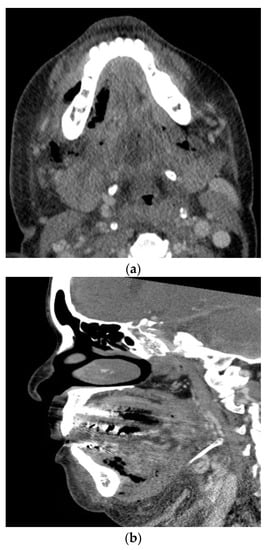

A feared complication of severe odontogenic infections is airway obstruction. When these infections involve deep fascial spaces, significant airway narrowing, and deviation may occur. Of particular importance is Ludwig’s angina which involves the submental space, the bilateral submandibular spaces, and the bilateral sublingual spaces Figure 2. The mandibular molars are the most common sources of infection leading to Ludwig’s angina. The clinical presentation includes pain, drooling, dysphonia, brawny neck edema, and tongue protrusion or elevation. The tongue is often pushed up and backward due to the fascial spaces involved, leading to airway obstruction. With improved imaging techniques, antibiotics, and a shift to early surgical treatment, the mortality rate from Ludwig’s angina has decreased from 50–54% to around 4–8% [,,].

Figure 2.

Axial (a) and sagittal (b) computed tomography scan views of a patient with Ludwig’s angina.